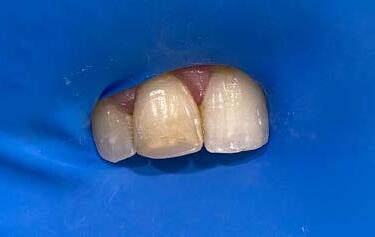

A 29-year-old male patient was referred for endodontic assessment and management of his teeth 11 and 12. Both teeth had history of root canal treatment in Spain many years ago. These teeth were asymptomatic until the patient got Covid, and they started to play up, as mentioned by the patient in the consultation session. Root canal treatments were done by a family dentist in Spain after the patient had a fall from his bicycle in his teen years.

Patient said that these teeth were tender upon biting and chewing on them for the past couple of days in March 2022. He found a dentist in Perth and they started the initial stage of the root canal treatment for him. On examination, tooth 11 had a mesioincisal tooth colored restoration with good quality, while the 12 did not have any restorations. Periapical view showed that tooth 11 had root filling whereas there was no sign of root filling material in the 12. However, there was a broken instrument inside the apical third of the root. The broken part was extruded almost 4mm from the radiographic apex of the 12.

Based on the endodontic examination, both teeth were diagnosed with previous root canal treatment and infected root canal system with chronic apical periodontitis and external apical inflammatory resorption due to breakdown of restorations and history of trauma. Different treatment modalities were explained to the patient.

Due to complexity of the case, the best treatment option was to:

• Investigation of both 11 and 12 to see whether they are suitable for further restoration or not,

• If these teeth can be saved, root canal re-treatment would be done. Fortunately, the endodontic investigation showed that these teeth could be saved as there was no further decay or cracks extending inside the roots.

For the root canal re-treatment, removal of the root filling materials was performed. To control the external apical inflammatory resorption, two rounds of intra-canal dressing of ledermix were done with intervals of 6 weeks for both teeth.

Then, the medicament was changed to calcium hydroxide, which was changed every 12-15 weeks. After 6 months, a periapical surgical procedure was performed in order to remove the broken instrument from the apical area of tooth 12 while tooth 11’s root canal was filled with GP cones and Ah-26 cement. Upon patient’s request, internal whitening was also done for his tooth 11, followed by a composite filling 1 week later.

Endodontic treatment of tooth 12 continued with long term calcium hydroxide until the 12’s root canal was eventually filled with GP cones and Ah-26 cement 6 months later.

Both teeth were sent to the referring dentist for continual of the treatment and placement of crowns.

First photo investigation session

After the first session of internal whitening

After the second session of internal whitening